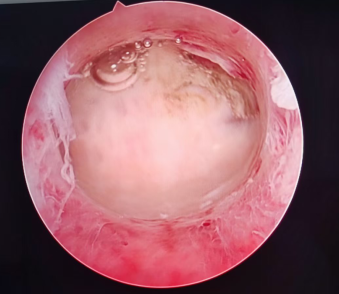

▲宫腔镜下子宫内膜息肉所见(术前、术后对比)